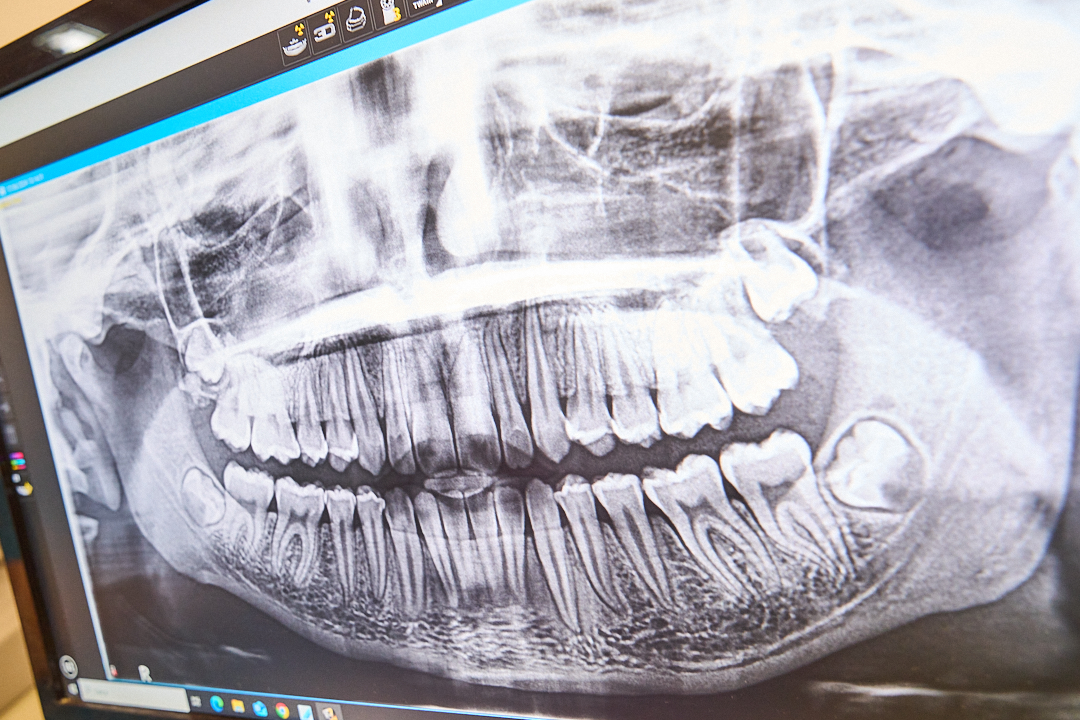

TAC CONE BEAM 3D

LA TAC Cone Beam 3D permette di garantire ai pazienti la massima qualità diagnostica con la minore esposizione ai raggix.

E’ una moderna apparecchiatura che fornisce all’odontoiatra immagini tridimensionali del cranio e della dentatura per mezzo di radiazioni acquisite da un sensore digitale ed elaborate da un computer.

L’esame CBCT consente al medico di visualizzare le strutture anatomiche di interesse e quelle critiche adiacenti in 3D, aiutandolo a definire in modo mirato la terapia e/o il trattamento chirurgico più adeguato per il caso: posizioni precise dei denti, delle strutture ossee, delle strutture anatomiche e delle strutture vitali. Inoltre, grazie al software  di ricostruzione 3D,  è possibile ricreare la bocca del paziente come in un oggetto tridimensionale.